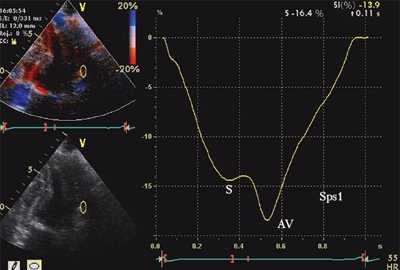

Оценивались также показатели тканевой допплерографии, характеризующие феномен ПСУ.

- Амплитуда постсистолического пика скорости, регистрируемого в фазу изоволюмического расслабления (Sps). Вычислялось отношение скоростей Sps/Sm.

- Форма кривой движения миокарда в течение сердечного цикла. Формы кривых движения миокарда в зависимости от наличия ПСУ подразделялись на 3 типа: "норма", "ступень" и "седло".

На рис. 3-5 приведены различные варианты ПСУ у больных с постинфарктным кардиосклерозом.

![Тканевая допплерография при постинфарктном кардиосклерозе. У больного с постинфарктным кардиосклерозом регистрируется высокоамплитудный пик постсистолической скорости (Sps)]()

б) При постинфарктном кардиосклерозе. У больного с регистрируется высокоамплитудный пик постсистолической скорости (Sps).

Вертикальная линия (AV) на рис. 3-5 соответствует времени закрытия аортального клапана. На представленных графиках также отмечается наличие базально-верхушечного градиента (снижение пиковых миокардиальных скоростей, продольного систолического смещения и деформации от основания к верхушке левого желудочка).